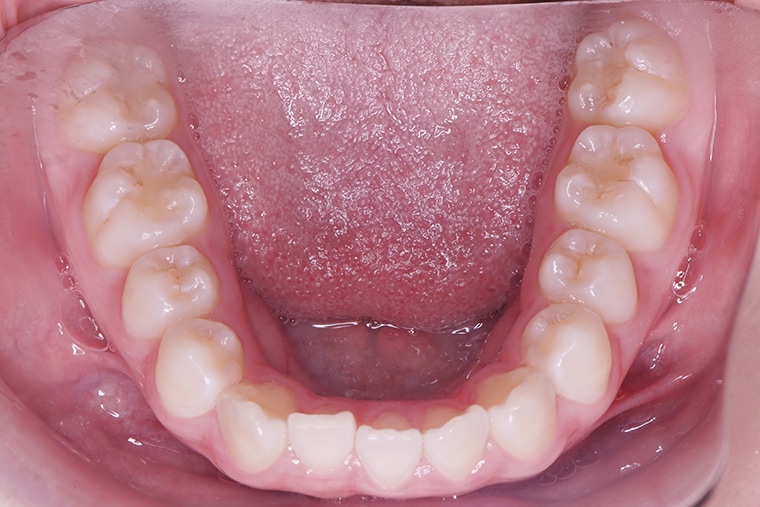

BEFORE